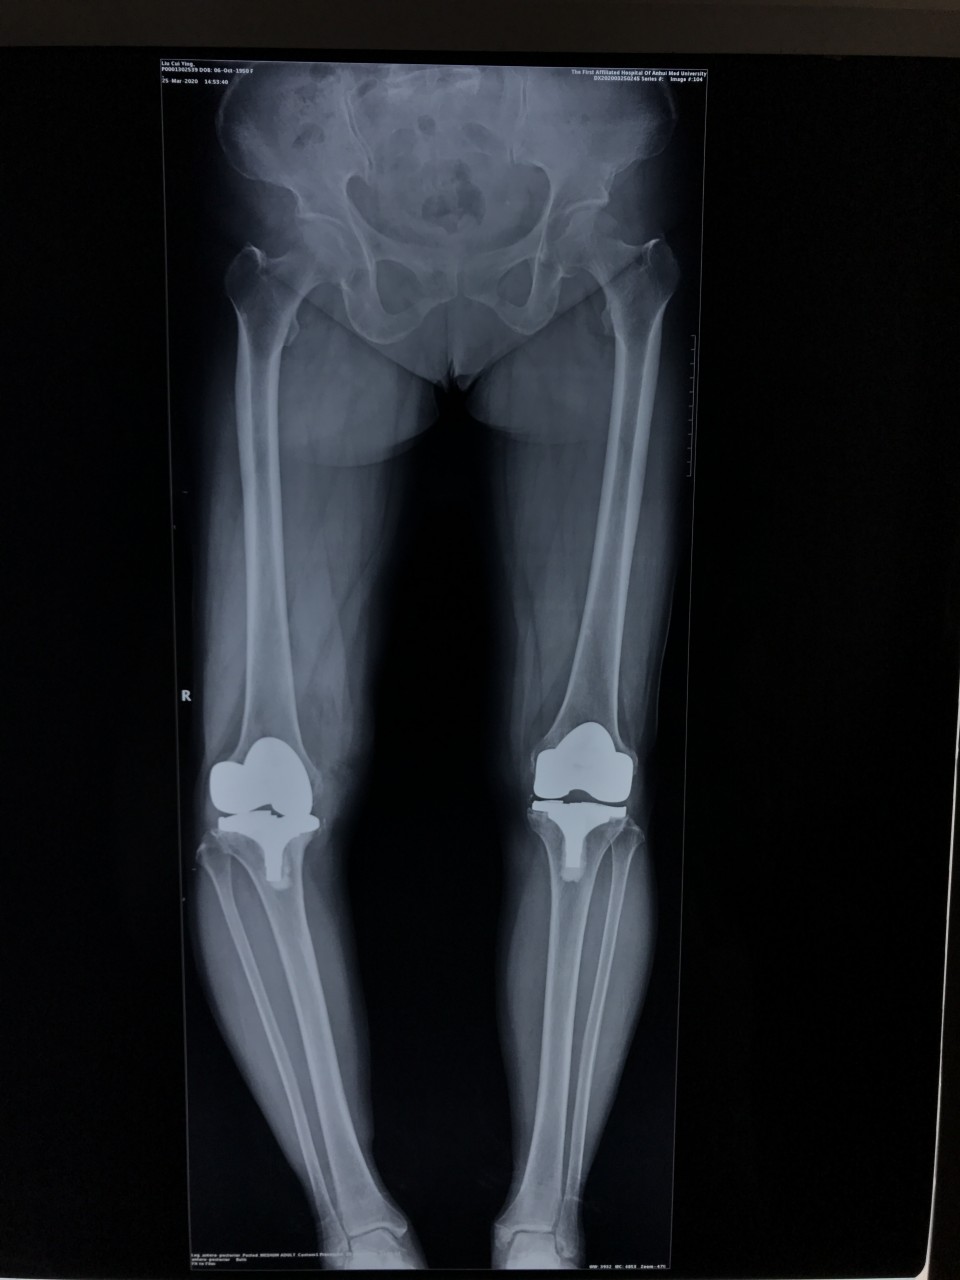

3月25日,一位69岁的女性患者因“右膝疼痛2年,加重伴活动受限1年”入院。术前摄片提示右侧膝关节假体松动。关节与显微修复外科胡孔足主任术前结合患者病史,体检及辅助检查,反复讨论,制定了精细的手术方案,术中假体安全取出,手术顺利。手术结束半小时,患者已经能够完全自主抬腿,屈曲。患者术后第二天下地正常行走。前后患者住院5天,快速康复出院。

人工关节翻修手术无论手术技术难度还是手术风险都要比初次人工关节置换大的多,而且感染风险也要比初次置换大,更有可能伴有大的骨缺损,手术方案需要精心制定。“快速康复外科”(ERAS)融合了麻醉、护理、康复、外科、以及营养等多学科理念。快速康复外科指采用证实有效的围手术期多模式优化管理措施,降低外科应激反应,降低术后疼痛,加速康复进程。ERAS应用于膝关节翻修患者具有明显优势,包括住院时间缩短、术后疼痛减轻、膝关节功能恢复优、术后失血量少、软组织损伤小、减少院内感染、住院费用少等,能够明显提高患者疗效及满意度。